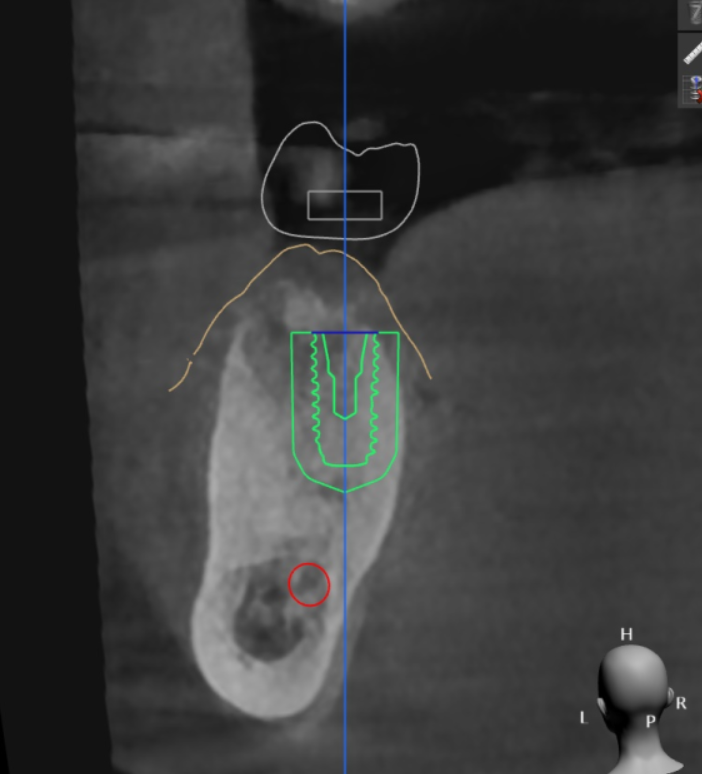

둔촌동 임플란트 진단을 진행하였습니다.

처음에 분석했을 때와

뼈 이식 후 모습

달라졌기에

2차 분석을 실시

23.09.11

바르디지털 치과인 만큼

내비게이션 임플란트 기술을 사용하여

수술 예측, 분석하였습니다.